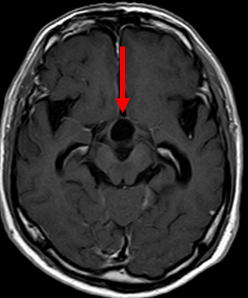

当院で施行された症例をお示しします。60歳男性、仕事でのミスが多くなり、認知症の原因精査のMRIにて、鞍上部に嚢胞を伴う腫瘍像を認め、水頭症も併発していました。(図1-a,b,c)

図1-a正中部に赤矢印の様に嚢胞性腫瘤を認めます。 |

図1-b 黄色矢印の如く脳室拡大も認めます。 |